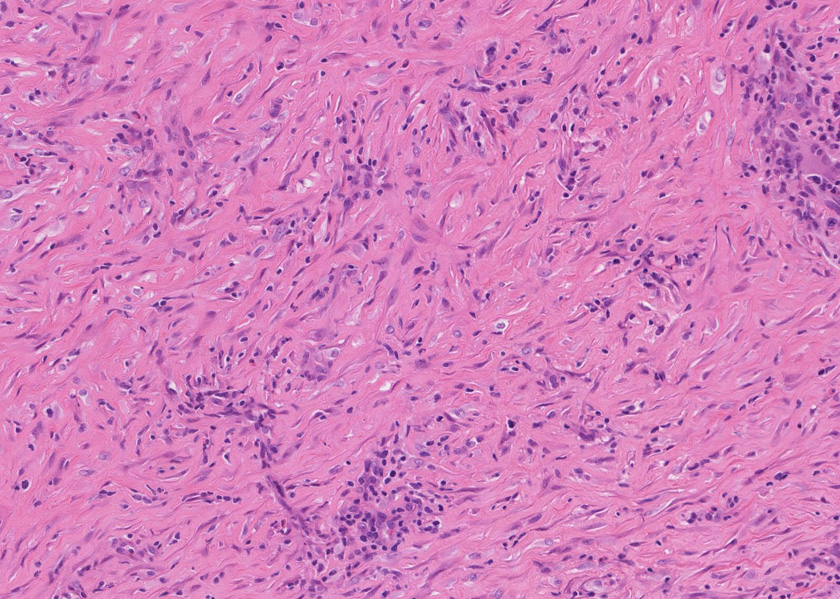

膵腺房間質にリンパ球, 形質細胞, 好中球の炎症細胞浸潤が認められる。

線維化組織に類円, 葉巻型淡明な核の紡錘型細胞が増生している。免染SMA陽性。血管周囲に慢性炎症あり。